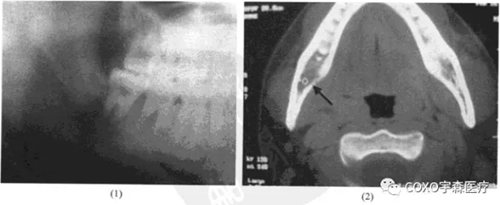

病例: 女性,48歲,右下后牙區(qū)腫痛2個月,曾在某醫(yī)院診斷為根尖周炎,抗炎治療無效,遂于6]近中取活檢,診斷為炎癥性改變,結(jié)核可疑,后轉(zhuǎn)來我院。

檢查:7-3]牙齦腫脹,54]缺失,6]呈殘冠狀,近中齦有炎性肉芽組織。x線片示:6]殘冠,根尖周及根分叉均有明顯骨質(zhì)吸收,雙頜下淋巴結(jié)腫大,質(zhì)中偏硬,臨床診斷為6]根尖周炎,頜下淋巴結(jié)核可能。